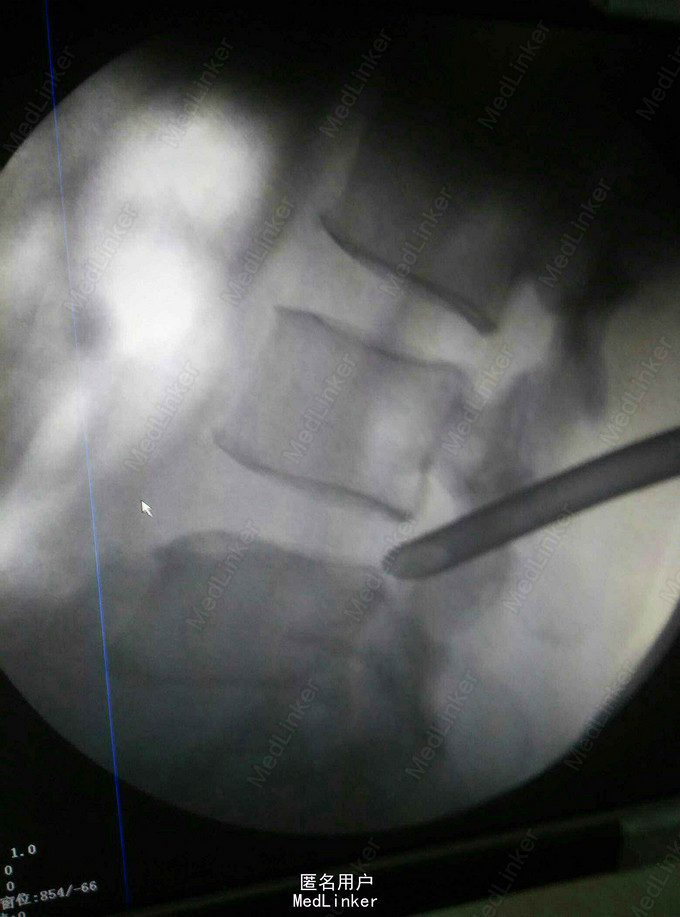

腰椎间盘突出,腰椎间孔镜治疗

术后症状明显缓解